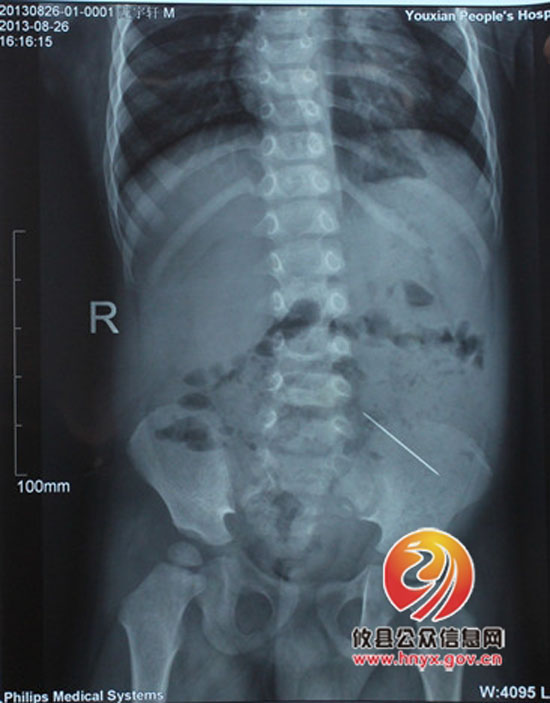

17:00,检查结果出来了,患儿x片显示回肠部位有近4cm的高密度阴影,正是这根可恶的绣花针!它已经在小轩轩的体内经过了一番从口腔经食道到胃、十二指肠、空肠、回肠的“长途跋涉”。